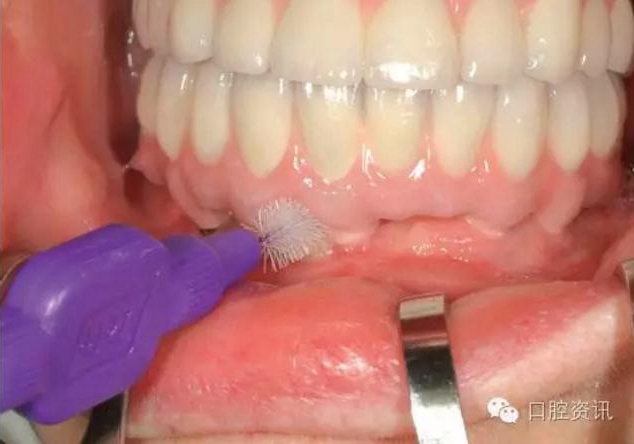

我們也希望您可以保質(zhì)保量地進(jìn)行口腔清潔,每日兩次刷牙、漱口以

及使用牙線、間隙刷等,都是最基本的要求。由于種植牙的構(gòu)造與天

然牙不同,有時您也需要一些特定的清潔工具。

16.jpg

圖16. 使用特制的間隙刷清潔